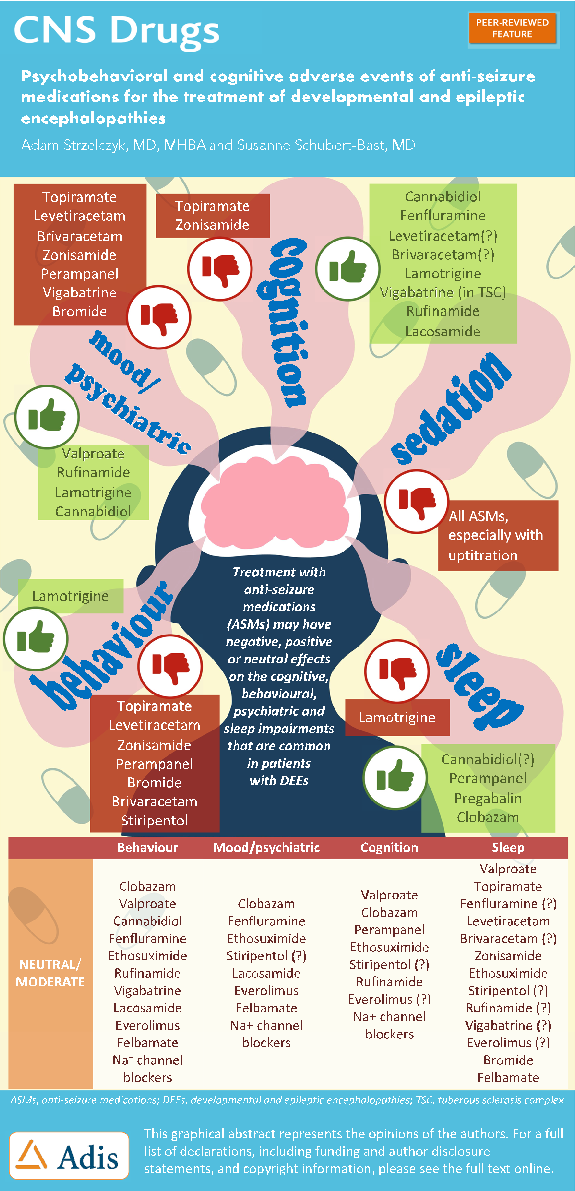

Developmental and epileptic encephalopathies involve severe drug-resistant epilepsy with significant neurodevelopmental comorbidities. This figure summarizes the psychobehavioural and cognitive adverse events associated with anti-seizure medications used to treat these rare childhood-onset syndromes.

Psychobehavioural and Cognitive Adverse Events of Anti-Seizure Medications for the Treatment of …